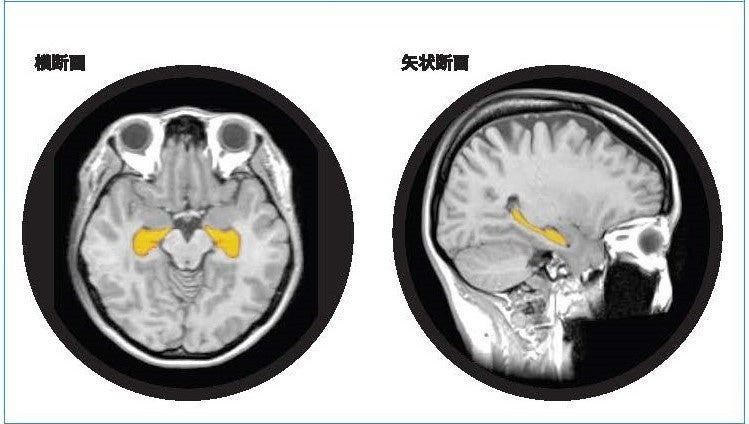

「BrainSuite®」とは

「BrainSuite®」は、頭部MR画像のAI解析技術等を利用することで海馬の体積や萎縮程度を測定・評価し、同性・同世代と比較した脳の健康状態を可視化します。受検者にはBrainSuite®専用会員ページ「MyPage」が用意され、脳の健康維持・改善方法についてアドバイスを提供します。20代から80代の幅広い年齢層を対象に、「生涯健康脳」の実現を最新の脳医学の観点からサポートする検査サービスです。

アルツハイマー型認知症は、顕著な脳萎縮を特徴としおり、脳の中でも海馬の萎縮は、20・30代から始まり、生活習慣要因によっては加齢性変化以上に萎縮が加速します。予防として健康なうちより生活習慣の改善をスタートすることがとても大切です。